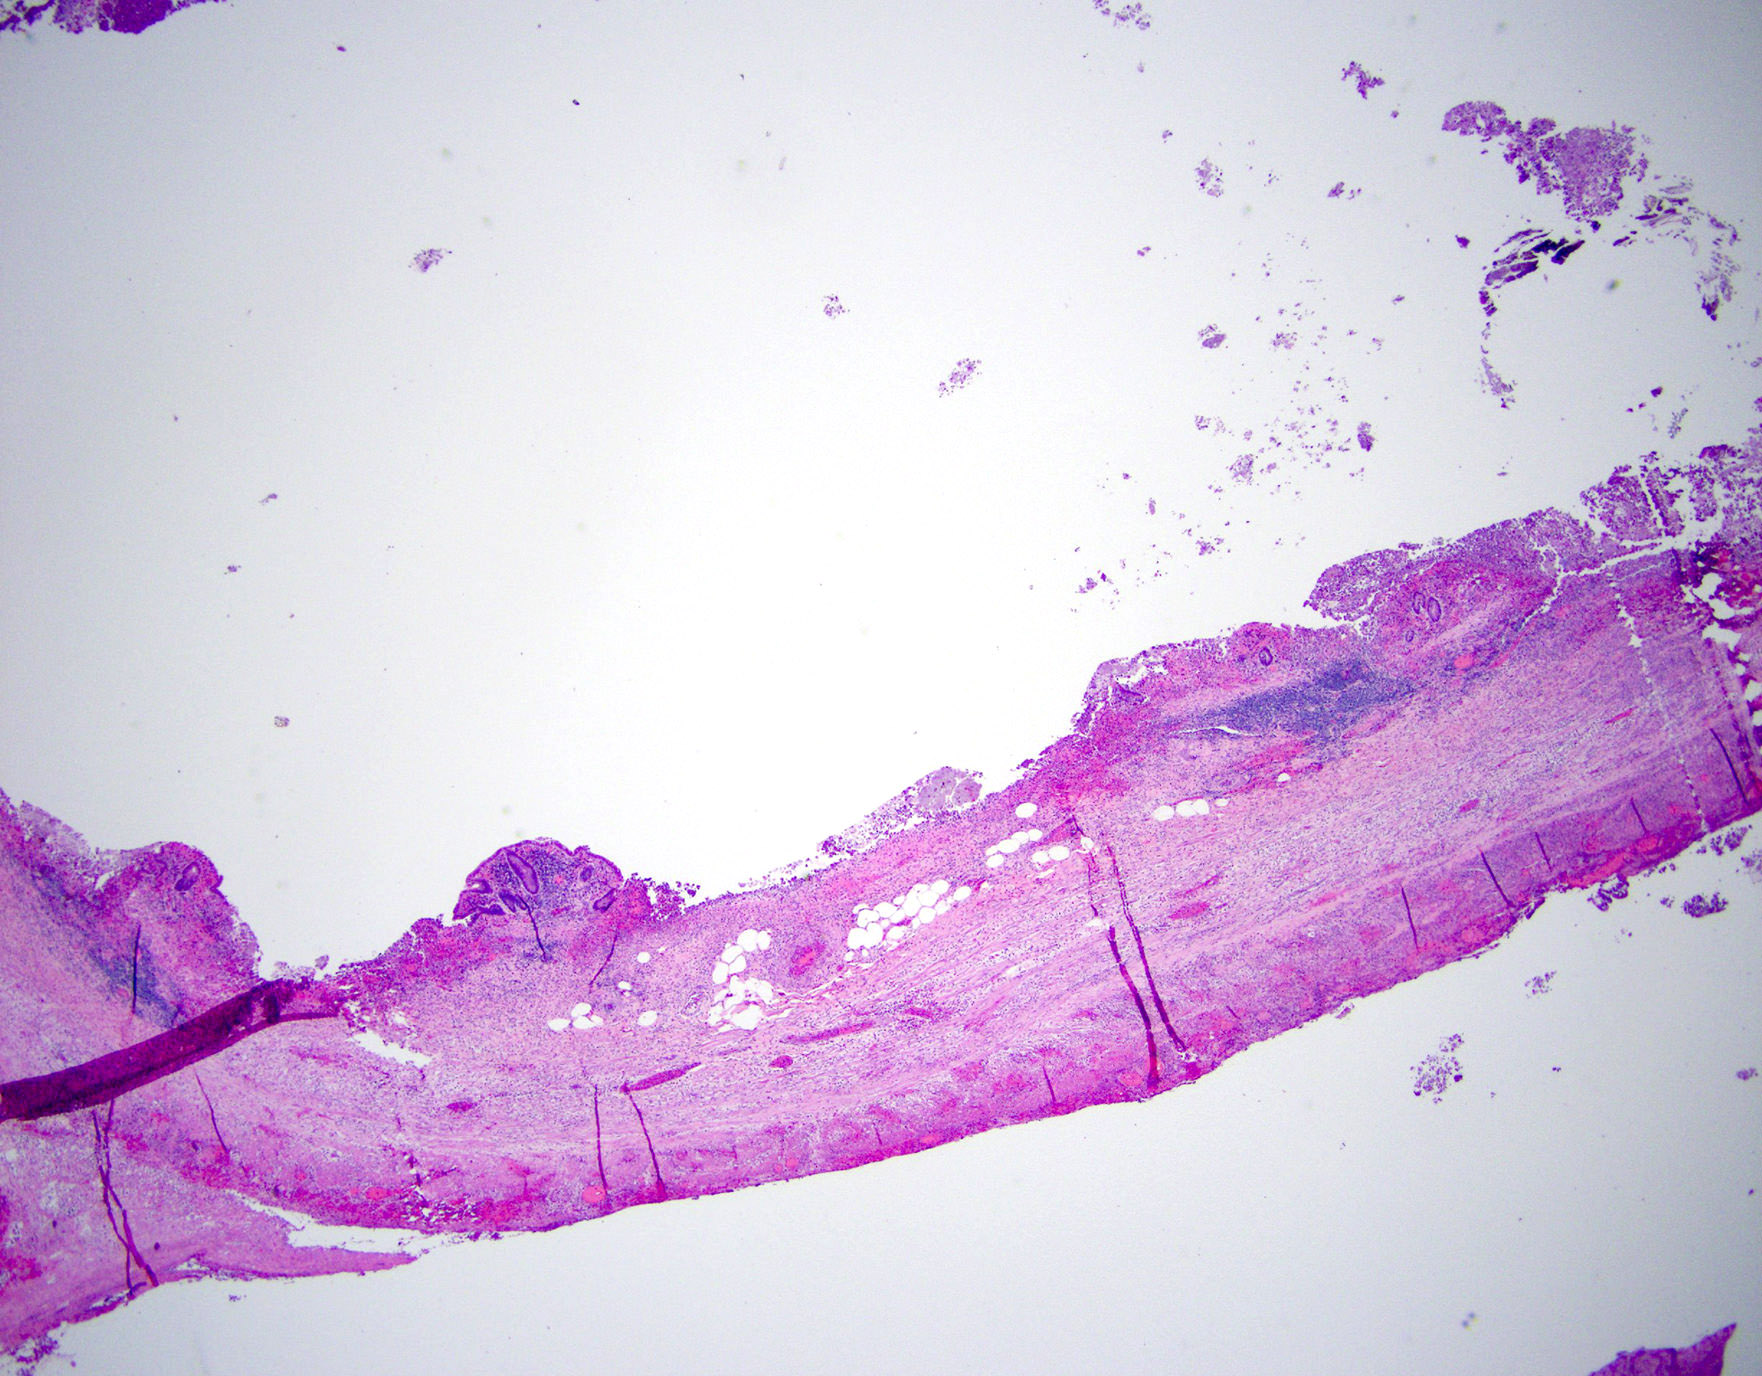

Microscopic (histologic) images

A 40 year old caucasian man presented into the emergency room with right lower quadrant pain associated with vomiting, abdominal tenderness, fever and moderate leukocytosis. Acute appendicitis was suspected and he underwent an appendectomy. His appendix was sent to pathology for histological evaluation. The H&E images are shown above. Which of the following is the most likely diagnosis?

A 35 year old woman presented with localized right lower quadrant abdominal pain for 1 day. She also presented with nausea, vomiting, menorrhagia and dizziness. She reported that she was actively menstruating and that these symptoms typically occurred monthly with menstruation but had been particularly severe in that month. CT scan showed thick walled appendix consistent with acute appendicitis. She underwent an appendectomy. The H&E images are shown above. Which of the following is the most likely diagnosis?